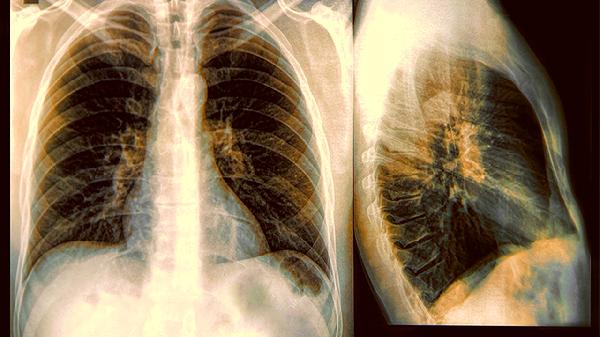

提醒睡觉时若出现6种迹象,或是肺癌前兆,希望你一个也不占!

平躺时突然发作的刺激性干咳,像是有羽毛在挠气管。与感冒咳嗽不同,这种咳嗽没有痰或仅有少量白色泡沫痰,且吃普通止咳药效果不明显。肺部肿瘤刺激支气管黏膜时,这种夜间"骚扰"会更加明显。

明明房间通风良好,却总觉得吸气不够深,需要刻意深呼吸才舒服。这种胸闷感在平躺时加重,坐起会缓解,可能与肿瘤压迫气管或胸腔积液有关。

仔细听的话,有些患者呼吸时会伴随轻微哮鸣音,像是从肺部深处传来的"吱吱"声。这是气流通过狭窄气道产生的异常呼吸音。

好端端睡着突然因呼吸困难而惊醒,像被人掐住了脖子。这可能是肿瘤阻塞大气道引起的急性缺氧,常见于中央型肺癌患者。